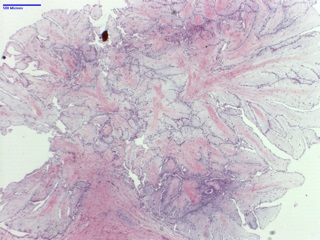

Papillary fibroelastoma is the most common valve tumor and is often discovered accidentally. When symptomatic, the most common presentation is stroke, followed by TIA and myocardial infarction. Grossly is classically described as “sea anemone”, with central stalk and fronds-like arms projecting outward, appearance that becomes more evident by placing the specimen in water.

Thrombi may occur on their surface and dislodged clots are responsible for embolic events. Most are smaller than 1cm but can be up to several cm large.

Histologically, they are composed primarily by collagen and elastin at the base with abundant mucopolysaccharide stroma, and outer endothelium expressing vimentin, factor VIII and CD34. The vasculature is minimal while myxomas (the main differential) are highly vascular lesions with typical “myxoma” cells and very rarely occur in heart valves.